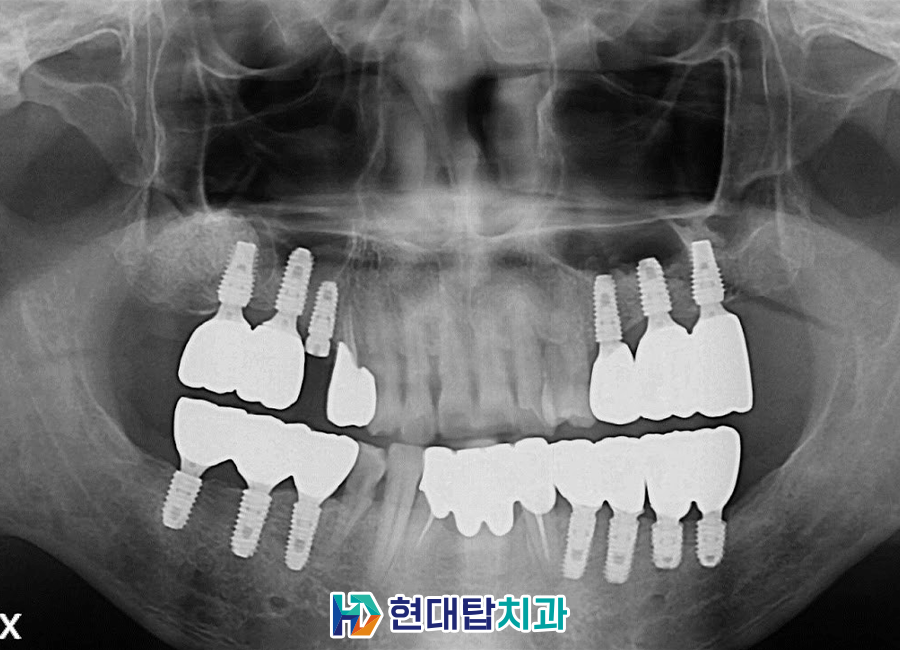

본 환자분은 50세 남성 환자분으로

본원에 내원 중이신 환자분의 소개로

내원해 주셨습니다.

전체적으로 잇몸뼈의 소실이 크셨고

아래 앞니는 많이 흔들려서 저절로

발치가 된 상태로

전반적인 치아의 상실과

충치, 치주 질환, 잇몸 염증으로 인해

잇몸뼈의 상태가 많이 좋지 않으셨습니다.

구강 내 전반적으로 치료할 곳이

많으셔서 부위를 나눠 치료를

진행하기로 하였습니다.

단단하게 뼈가 만들어진 후

위쪽 임플란트를 식립한 모습입니다.

아래쪽은 중간 연결기둥을 체결하였고

충치치료들을 완료하였습니다.

최종 보철까지 완성된 모습입니다.